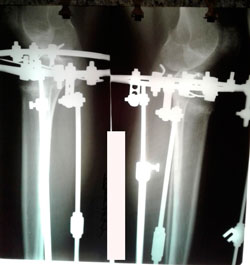

Исходник - 42 года.

Дата операции - 27.05.2020

Красивые ноги получились!